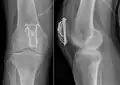

Zuggurtungsosteosynthese mit zusätzlichen axialen Bohrdrähten

Das Ziel der Zuggurtung wird nur erreicht, wenn die Knochensubstanz der Kniescheibe und der Frakturtyp eine Kompressionsstabilität und Rotationsstabilität sicherstellen. Bestehen Zweifel an der Stabilität, kann diese durch zusätzliches Einbringen von axialen kräftigen Bohrdrähten (Kirschnerdrähten|) erreicht werden. Die Bohrdrähte werden nach Reposition der Fraktur von der Oberkante in die Kniescheibe eingebohrt, überqueren die Frakturlinie und verlassen die Kniescheibe wieder am Ansatz der Patellarsehne. Die Drähte sollten im Abstand von etwa 2 cm parallel eingebohrt werden. Die Drahtschlinge der Zuggurtung wird in diesem Fall nicht nur um die Sehneneinstrahlung in die Kniescheibe, sondern zusätzlich über die Bohrdrahtenden gelegt, was die Befestigung verbessert. Ein entscheidender Begleiteffekt dieser Operationsvariation ist, dass auch bei in Streckung des Knies reduzierter Zugspannung der Cerclage eine garantierte Position der Gelenkfläche erreicht wird. Dieser Effekt ist so wichtig, dass die Operation der Patellazuggurtung heute sehr häufig in dieser Variation durchgeführt wird.

Zuggurtungs-osteosynthese einer einfachen Patellaquerfraktur -

Erweiterte Zuggurtungs-osteosynthese einer Patella-Querfraktur mit axialen Bohrdrähten